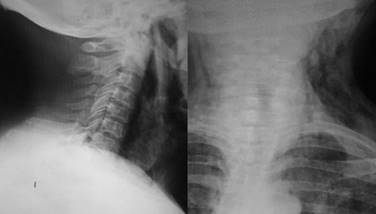

Se realizaron en total 18 procedimientos, se consideró como complicación sólo un paciente (7.1%), quien presentó sangrado importante, mismo que se controló, pero impidió en el procedimiento inicial completar adecuadamente la miotomía, por lo que se reintervino a las 24 horas para completar ésta. Durante los procedimientos, dos pacientes tuvieron enfisema subcutáneo (un paciente femenino de 74 años y uno masculino de 57 años), los cuales fueron tratados de forma conservadora mediante la administración de una cefalosporina de tercera generación, así como control radiográfico para medición del enfisema subcutáneo (Figura 6). No se presentaron complicaciones mayores como mediastinitis, hemorragia incoercible o perforación que requirieran cambiar el tratamiento endoscópico por el quirúrgico de urgencia o programado. La mejoría de la disfagia en todos los casos fue inmediata y en las consultas subsecuentes refirieron haber aumentado de peso, además se realizó endoscopia y trago de material de control (Figura 7).